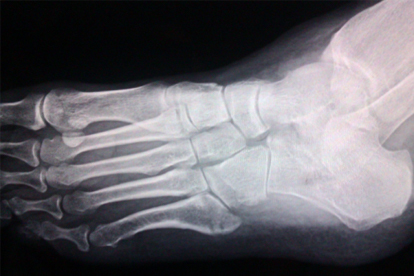

脚骨折后夜间发热可能与局部炎症反应、血液循环改变或感染有关。骨折后机体启动修复机制,炎症因子释放可能导致体温波动,夜间静息时症状感知更明显。若伴随红肿加剧、脓性分泌物或持续高热,需警惕感染。